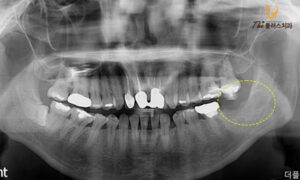

엑스레이 촬영을 진행해 보니

환자분께서 말씀해 주신 부위의

사랑니로 인해 인접한 큰 어금니가

충치가 생긴 상황으로 보였고,

큰 어금니는 충치가

많이 진행되어 있는 상태였습니다.

환자분의 경우처럼

누워있는 방향으로 난 사랑니는

사이에 음식물이 끼기 쉽고,

양치 관리가 어려워 충치가 생기기 쉽습니다.